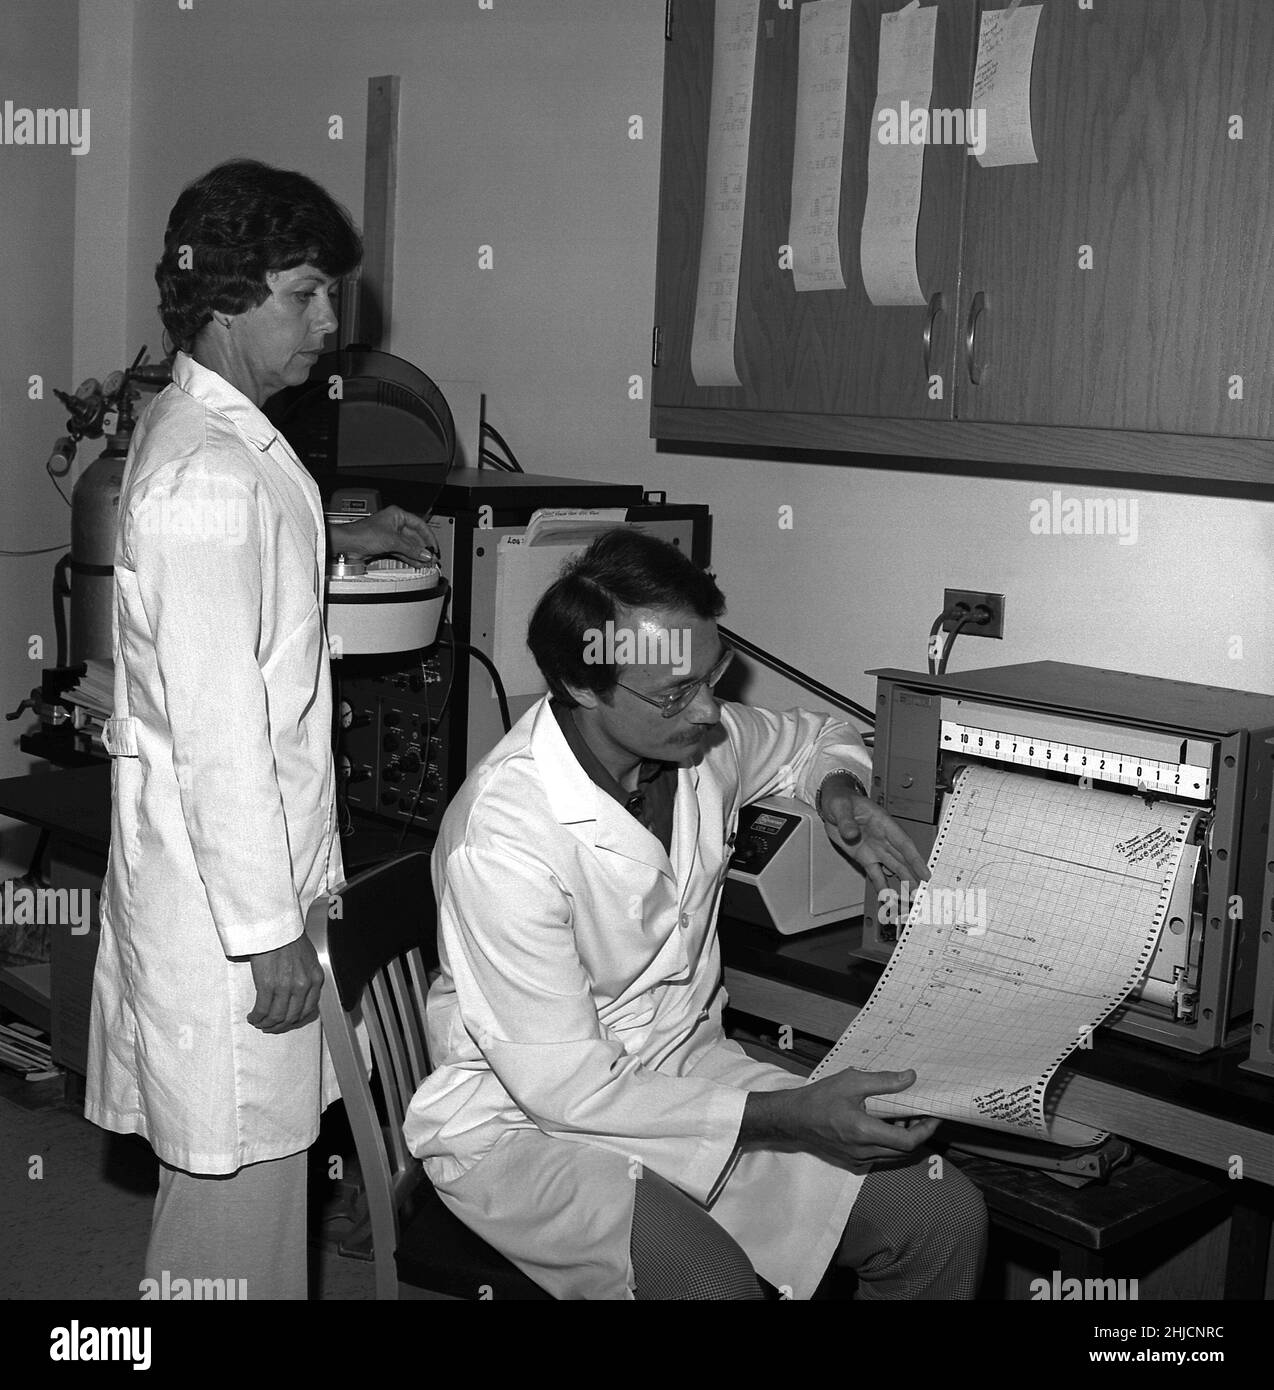

Dieses Bild aus dem Jahr 1977 zeigt die Mikrobiologen Joseph E. McDade (links) und Charles C. Shepard (rechts), die den Erreger isolieren, der den Ausbruch der Legionäre 1976 auf einer Tagung der American Legion in Philadelphia verursacht hatte. Sie stellten fest, dass die Ursache eine Art von Bakterien war, die sie Legionella pneumophila nannten. Stockfotohttps://www.alamy.de/image-license-details/?v=1https://www.alamy.de/dieses-bild-aus-dem-jahr-1977-zeigt-die-mikrobiologen-joseph-e-mcdade-links-und-charles-c-shepard-rechts-die-den-erreger-isolieren-der-den-ausbruch-der-legionare-1976-auf-einer-tagung-der-american-legion-in-philadelphia-verursacht-hatte-sie-stellten-fest-dass-die-ursache-eine-art-von-bakterien-war-die-sie-legionella-pneumophila-nannten-image458814420.html

Dieses Bild aus dem Jahr 1977 zeigt die Mikrobiologen Joseph E. McDade (links) und Charles C. Shepard (rechts), die den Erreger isolieren, der den Ausbruch der Legionäre 1976 auf einer Tagung der American Legion in Philadelphia verursacht hatte. Sie stellten fest, dass die Ursache eine Art von Bakterien war, die sie Legionella pneumophila nannten. Stockfotohttps://www.alamy.de/image-license-details/?v=1https://www.alamy.de/dieses-bild-aus-dem-jahr-1977-zeigt-die-mikrobiologen-joseph-e-mcdade-links-und-charles-c-shepard-rechts-die-den-erreger-isolieren-der-den-ausbruch-der-legionare-1976-auf-einer-tagung-der-american-legion-in-philadelphia-verursacht-hatte-sie-stellten-fest-dass-die-ursache-eine-art-von-bakterien-war-die-sie-legionella-pneumophila-nannten-image458814420.htmlRM2HJCPD8–Dieses Bild aus dem Jahr 1977 zeigt die Mikrobiologen Joseph E. McDade (links) und Charles C. Shepard (rechts), die den Erreger isolieren, der den Ausbruch der Legionäre 1976 auf einer Tagung der American Legion in Philadelphia verursacht hatte. Sie stellten fest, dass die Ursache eine Art von Bakterien war, die sie Legionella pneumophila nannten.